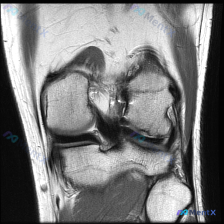

这是一份膝关节MRI单张冠状位T1加权图像的读片分析需求,题干提示可能存在「软骨异常」,需要我们判断影像上的实际表现。

- 骨骼结构:股骨远端内外髁、胫骨平台轮廓清晰,骨皮质连续,没有骨折线或骨质破坏;骨髓腔内是T1加权典型的脂肪高信号,没有明显骨髓水肿低信号改变

- 半月板:内外侧半月板都保持正常三角形形态,信号均匀低信号,边界清晰,没有信号增高或者形态改变,看不到明确撕裂征象

- 侧副韧带:内外侧副韧带走行连续,是正常条状低信号,没有增粗或者信号异常

- 交叉韧带:这个层面只显示了髁间窝内部分,虽然因为切层和部分容积效应没法评估全程,但可见部分没有连续性中断

- 关节软骨与关节腔:股骨髁和胫骨平台的关节软骨没有看到明显局灶性缺损或者变薄,关节间隙宽度正常,也没有显著异常积液

现在回到最开始的问题:这张图到底有没有显示软骨异常?

初步判断:题干提示「软骨异常」,第一反应是去软骨区域找缺损、信号改变,但扫完整个图像,所有可见软骨都是正常形态

线索拆解与矛盾验证:这里出现了一个关键矛盾——题干提示异常,但影像客观表现不支持。我们需要拆解可能的原因:

- 是不是我看错了?再复核一次:软骨确实没有形态和信号异常,半月板韧带骨骼也都没问题

- 是不是信息本身的问题?我们拿到的只有单张T1冠状位,本身就有局限性

- 方向1:支持软骨异常:没有任何客观影像证据支持,所有可见软骨都正常

- 方向2:正常膝关节结构:所有可见结构形态信号都符合正常表现,支持这个判断

- 方向3:隐匿软骨异常:T1序列本身对软骨软化、早期磨损这类病变不敏感,单一层面也可能漏掉病变,所以不能完全排除,但现有图像不支持

基于现有这张图像的客观发现,没有证据支持「软骨异常」的诊断,目前最可能的情况就是这张图像显示膝关节大致正常。

但我们必须明确局限性:仅凭这一张T1冠状位,不能完全排除其他序列/层面存在的软骨病变或者其他软组织损伤。